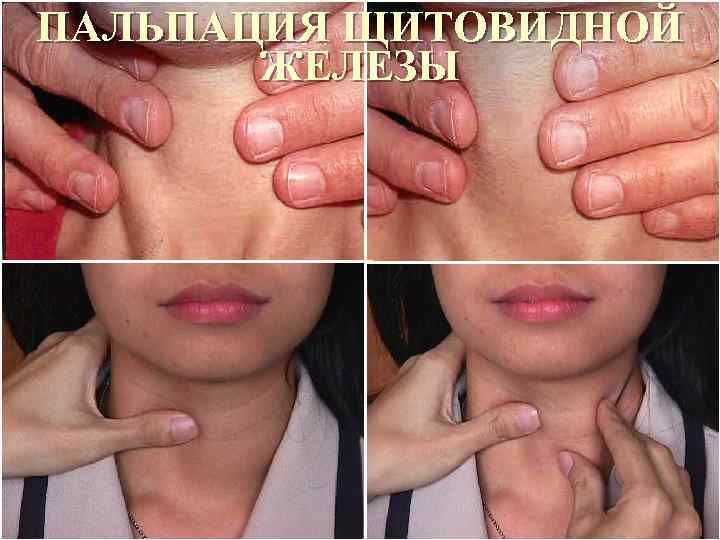

ПАЛЬПАЦИЯ ЩИТОВИДНОЙ ЖЕЛЕЗЫ